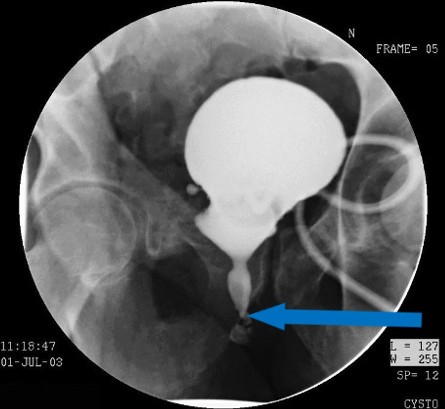

Ο συνδυασμός ανιούσας (Εικόνα 1) και κατιούσας (Εικόνα 2) ουρηθρογραφίας αναδεικνύει αναστομωτικό στένωμα μήκους ενός εκατοστού. Η προσπάθεια καθετηριασμού με καθετήρα 10 French, ώστε να ακολουθήσει διαστολή του στενώματος αποτυγχάνει.

Εικόνα 1 Ανιούσα ουρηθρογραφία (Το μπλέ βέλος δείχνει το σημείο του στενώματος)